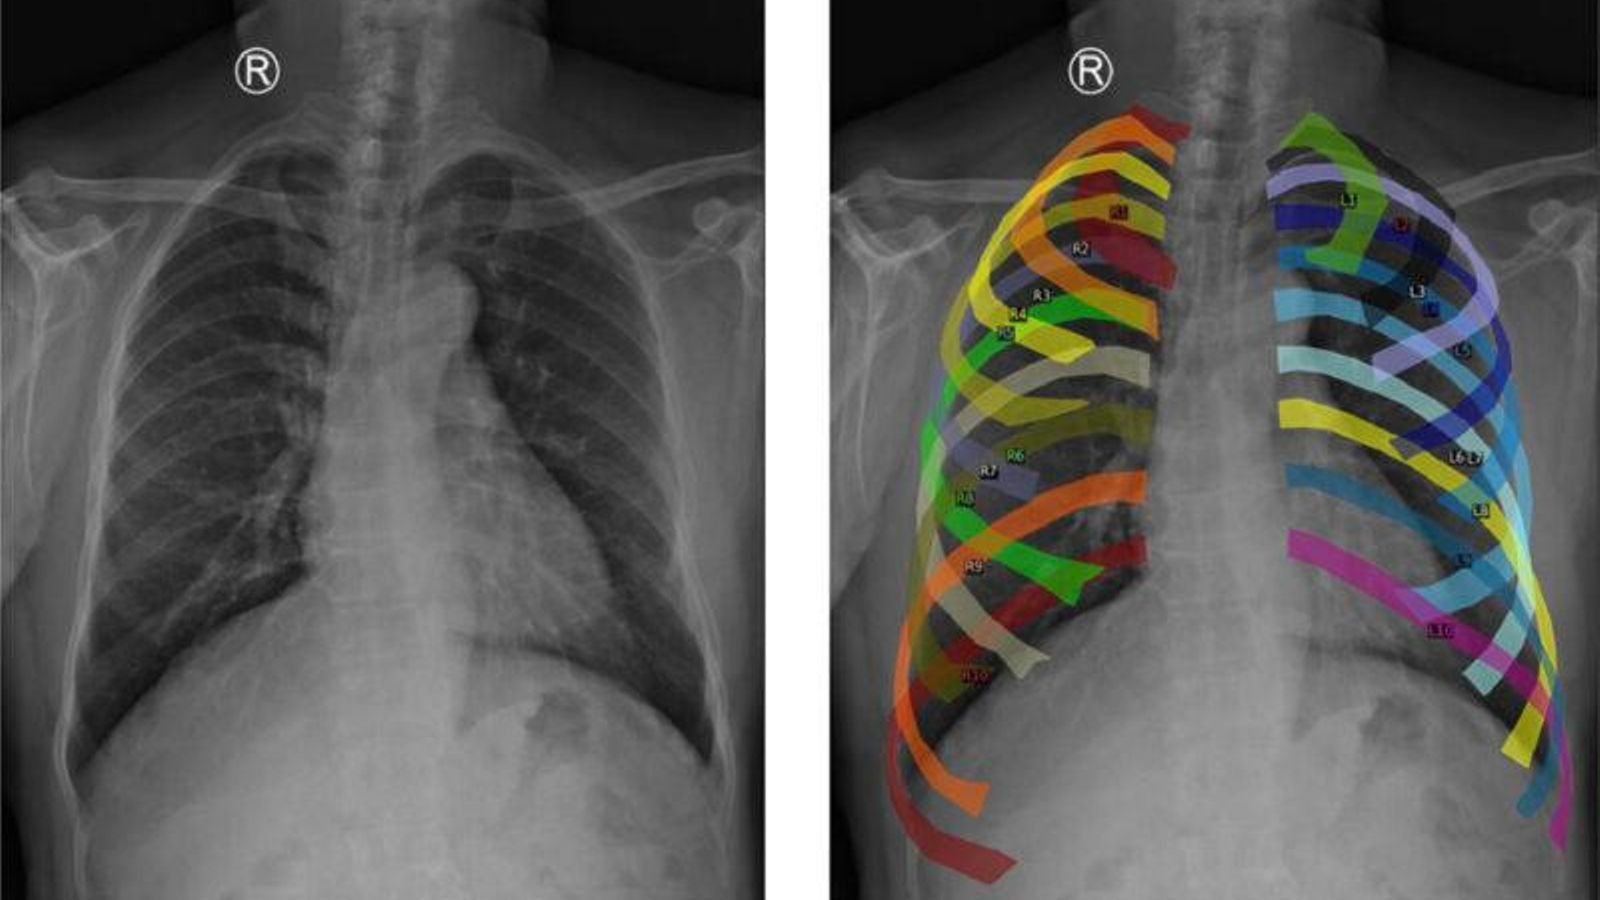

Para una mejora en el entrenamiento del modelo, se han empleado datos de distintos centros hospitalarios y una estrategia conocida como aumento de datos, en las que se segmentan las costillas y se alinean puntos clave del tórax para generar nuevas imágenes homogéneas desde una perspectiva anatómica. Con esto, se consigue que sea robusto, incluso ante radiografías de distintos hospitales, de diferente resolución o adquiridas con otro equipamiento. El sistema aprende mejor y funciona de forma más generalizada.